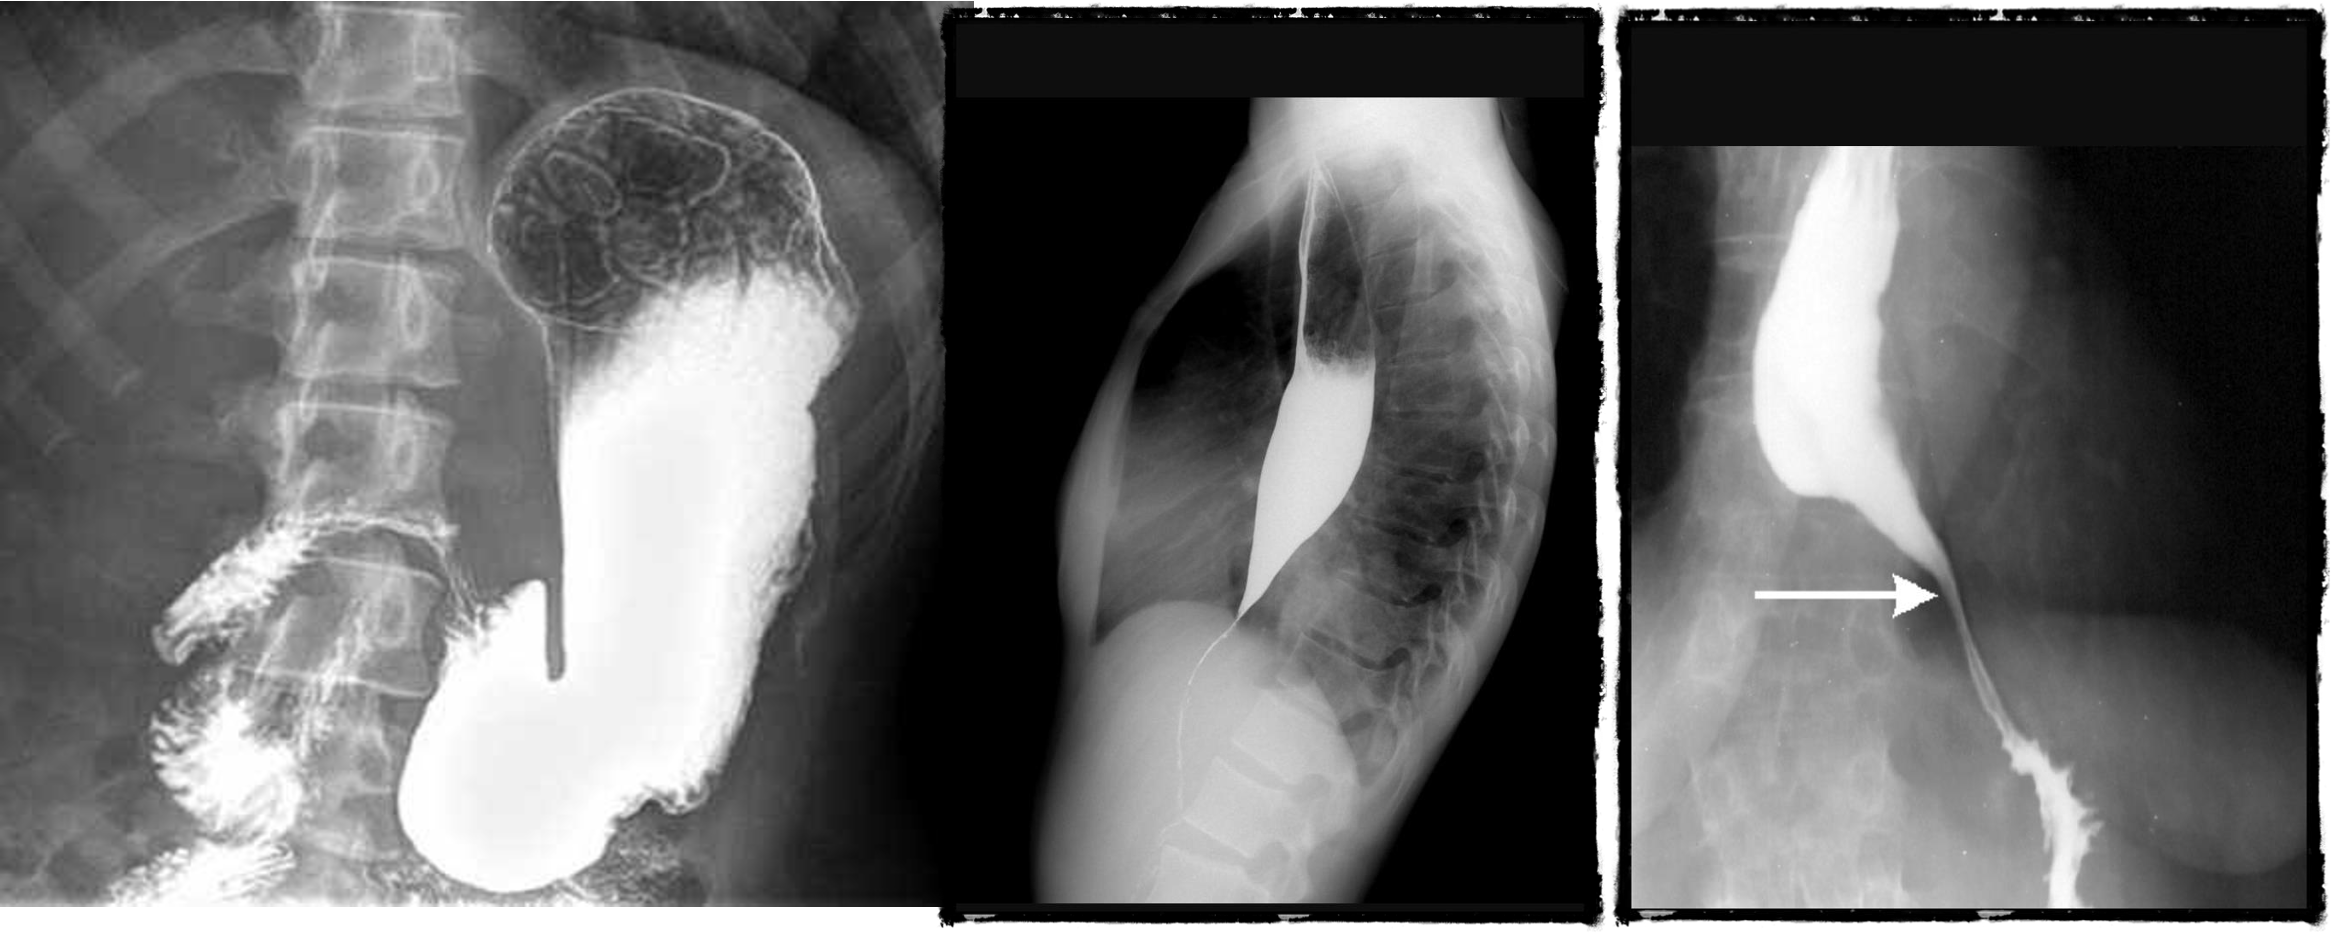

Contrast Imaging

Gastrograffin swallow, Barium meal / enema

- Visualize GI tract

- Single/ double contrast

- Inferior to endoscopy

Modality: Gastrography swallow / Barium Enema Findings: apple core / out pouching lesions Differentials: colon cancer / diverticulum

- barium swallow - zenkers diverticulum

- b swallow - diltation upper, stricture (diff cancer)

- normal (mucosal fold roge)

- dilated esophagus, stricture, bear beak/rat tail sign = aclasia